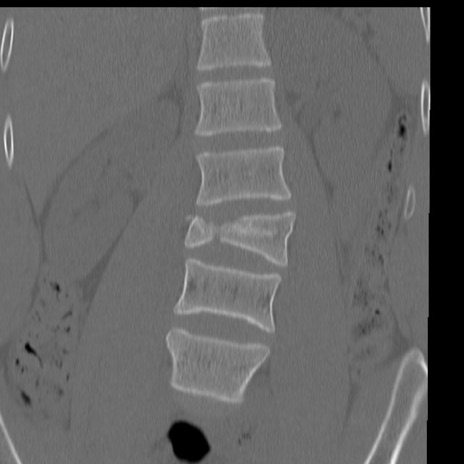

症例3 腰椎CT(冠状断像)

腰椎CT

矢状断像